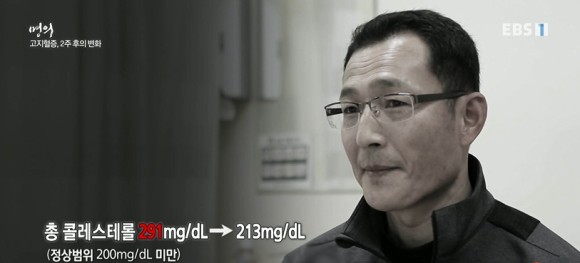

환자사례 4 마른 체형의 고지혈증 남자, 총콜레스테롤 291, LDL 196

무조건 약을 먹는 것보다 2주간 생활습관 개선을 먼저 시도하고 콜레스테롤 수치 변화를 관찰합니다. 잡곡밥, 생선, 채소, 과일 등을 충분히 섭취하고 육류, 기름진 음식, 버터 제한합니다. 하루 세 번 식사, 인스턴트 안 먹기, 식후 운동(301시간 걷기, 근력운동) 등.

고지혈증 약을 복용하지 않고 2주간의 식사와 운동요법을 병행한 결과 엄청난 결과가 있군요.총 콜레스테롤 291 → 213으로 저하됩니다.